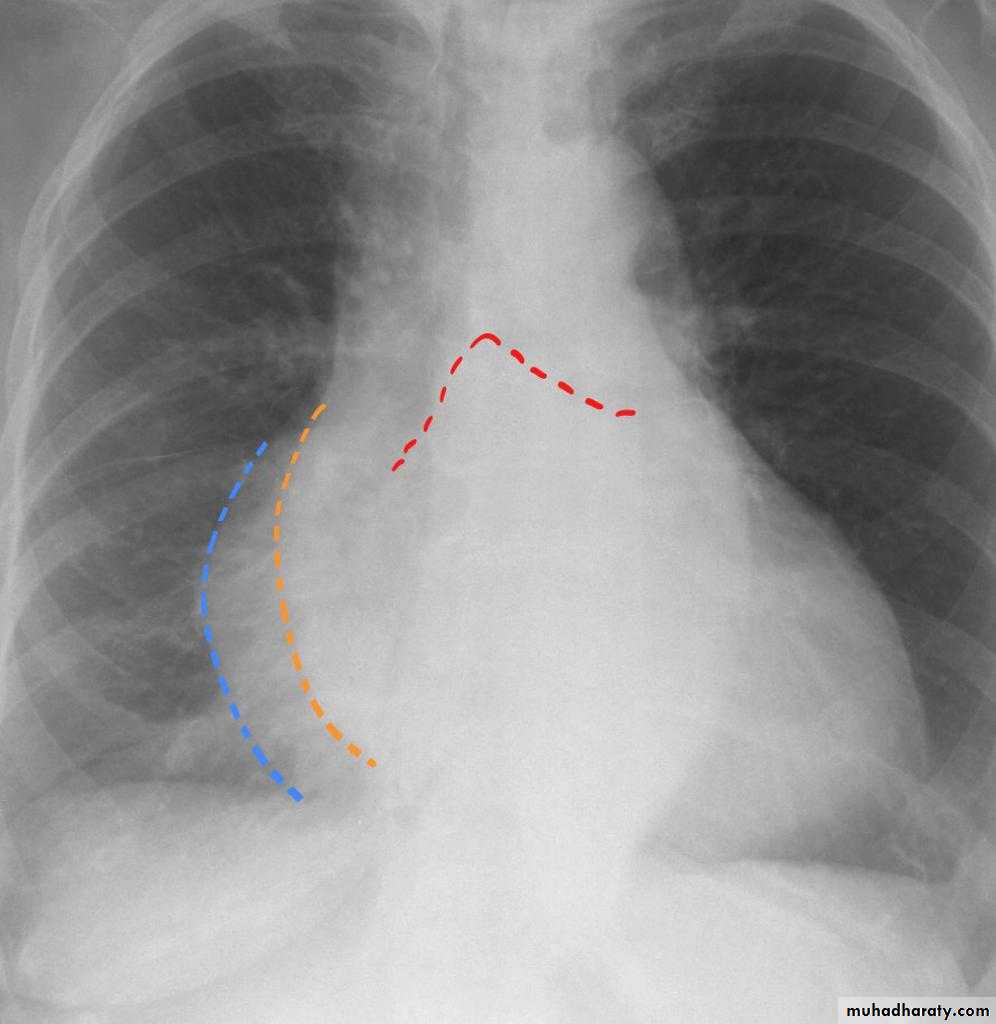

Radiographic featuresPlain film

Typical radiographic features of mitral regurgitation include :

frontal projection

1.left atrial enlargement

convexity or straightening of the left atrial appendage just below the main pulmonary artery (along left heart border)

2.double density sign: the right side of the enlarged left atrium pushes into the adjacent lung and creates an addition contour superimposed over the right heart

3.elevation of the left main bronchus and splaying of the carina

4.upper zone venous enlargement due to pulmonary venous hypertension

5.left ventricular enlargement is also eventually present due to volume overload

6.Features of pulmonary oedema may also be present.